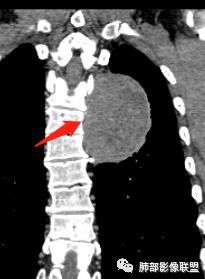

红日东升:左侧胸椎旁肿块,边缘清晰光整,冠状位见D字征,未见支气管进入,肺组织受压表现,定位肺外。轻度强化,密度稍不均匀,临近肋骨变细,未见肺动脉供血,考虑良性肿瘤,神经源性可能。右肺下叶病灶,轻度强化,血管显影,边缘平直、凹陷,考虑炎性病变。

张立:左侧胸椎旁肿块,边缘清晰光整,冠状位见D字征,未见支气管进入,肺组织受压表现,定位肺外。轻度强化,密度稍不均匀,,未见肺动脉供血,神经源性肿瘤,节细胞神经瘤可能。右肺下叶病灶,轻度强化,血管显影,边缘平直、凹陷,TB可能。

崇军:左侧胸椎旁肿块,边缘清晰光整,有胸膜尾征,冠状位为D字征,定位肺外。轻度强化,密度稍不均匀,似乎看到肋间动脉供血,未见肺动脉供血,考虑良性肿瘤,神经源性可能。右肺下叶病灶,轻度强化,血管显影,边缘平直、凹陷,层面太少,暂时考虑炎性病变。

长沟流月去无声:中年男性,慢咳起病,左后纵隔可见一大占位,D字征,胸膜掀起,有胸膜尾征,附近肺组织受挤压,血管纹理纠集,瘤肺界面清晰,较均匀轻-中度强化,瘤肺表面可见线样不张之强化影,供血血管来源不易确定,冠状位似乎见一纵隔血管出入,综合考虑神经源性肿瘤:神经纤维瘤,神经鞘瘤?右下外斑片密度影,估计炎性,但本次手术应该未处理。

ZK金:定位:左肺下叶后综合脊柱旁肺外肿块,胸膜尾征,D字征,瘤肺交界面清晰,肺组织受压。影像表现:边界清晰,密度均匀,上下经线略横经。首先考虑神经源性肿瘤,神经节细胞瘤首选,鞘瘤和孤立性纤维瘤鉴别诊断。右肺下叶考虑炎症。

椎间孔很有价值吧

如果椎间孔增大,应该考虑神经源性的

大雄:所以还是得看潘老师说的椎间孔

问题是大病灶,而且椎间孔没累及

5.相邻椎间孔未见扩大,也未见块影延入椎管,易起自于神经根的鞘瘤似乎找不到相关支持点。

6.未提供矢状位骨窗图像,如在肋骨内下缘观察到压迹有助于肋间神经的鞘瘤的判断,这是因为二者之间密切的毗邻关系。